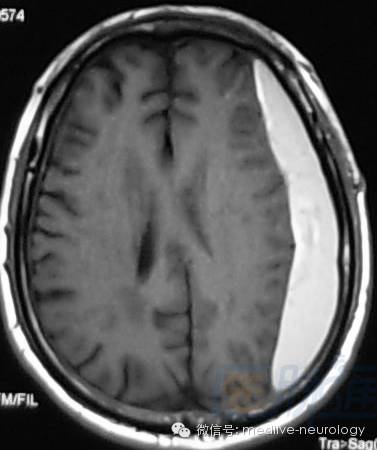

然后解决第三个问题,轻松一下,图来啦,让我们巩固一下今天学习的成果,均为先T1,后T2。

亚急性早期(3-7d): 脑桥

亚急性晚期(7-14d): 左硬膜下